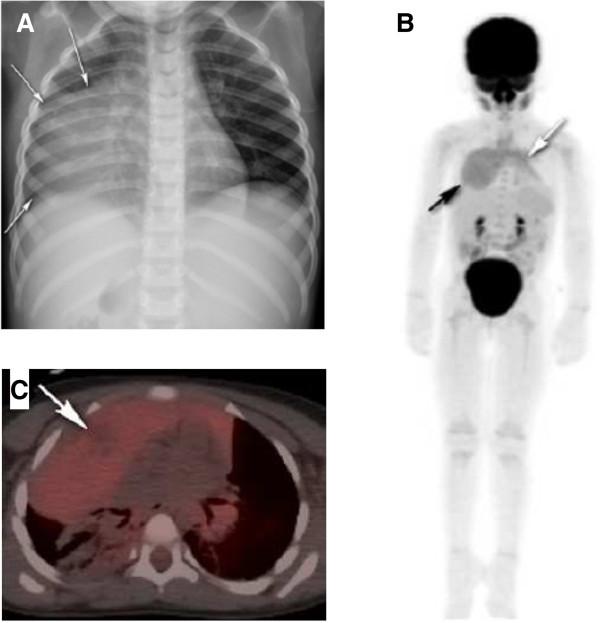

A 2 year old girl presented with new onset of emesis and constipation leading to the incidental discovery of an anterior mediastinal mass on radiograph. Chest computed tomography revealed cystic components within the mass concerning for a malignancy. Biopsy of the lesion and bone marrow aspiration and biopsy were negative but there was concern that the mediastinal biopsy may have missed the malignant component of the lesion. Hence, a positron emission tomography scan was obtained that showed mild homogeneous fluorodeoxyglucose 18F avidity within the mass similar to that of normal thymus. The diagnosis of benign hyperplastic thymus was made.

一名2岁女孩因新出现呕吐和便秘,在胸部X线检查时偶然发现前纵隔肿块。胸部计算机断层扫描显示肿块内有囊性成分,怀疑为恶性肿瘤。病变活检及骨髓穿刺活检均为阴性,但担心纵隔活检可能遗漏了病变的恶性成分。因此,进行了正电子发射断层扫描,结果显示肿块内氟脱氧葡萄糖18F摄取轻度均匀,与正常胸腺相似。诊断为良性增生性胸腺。